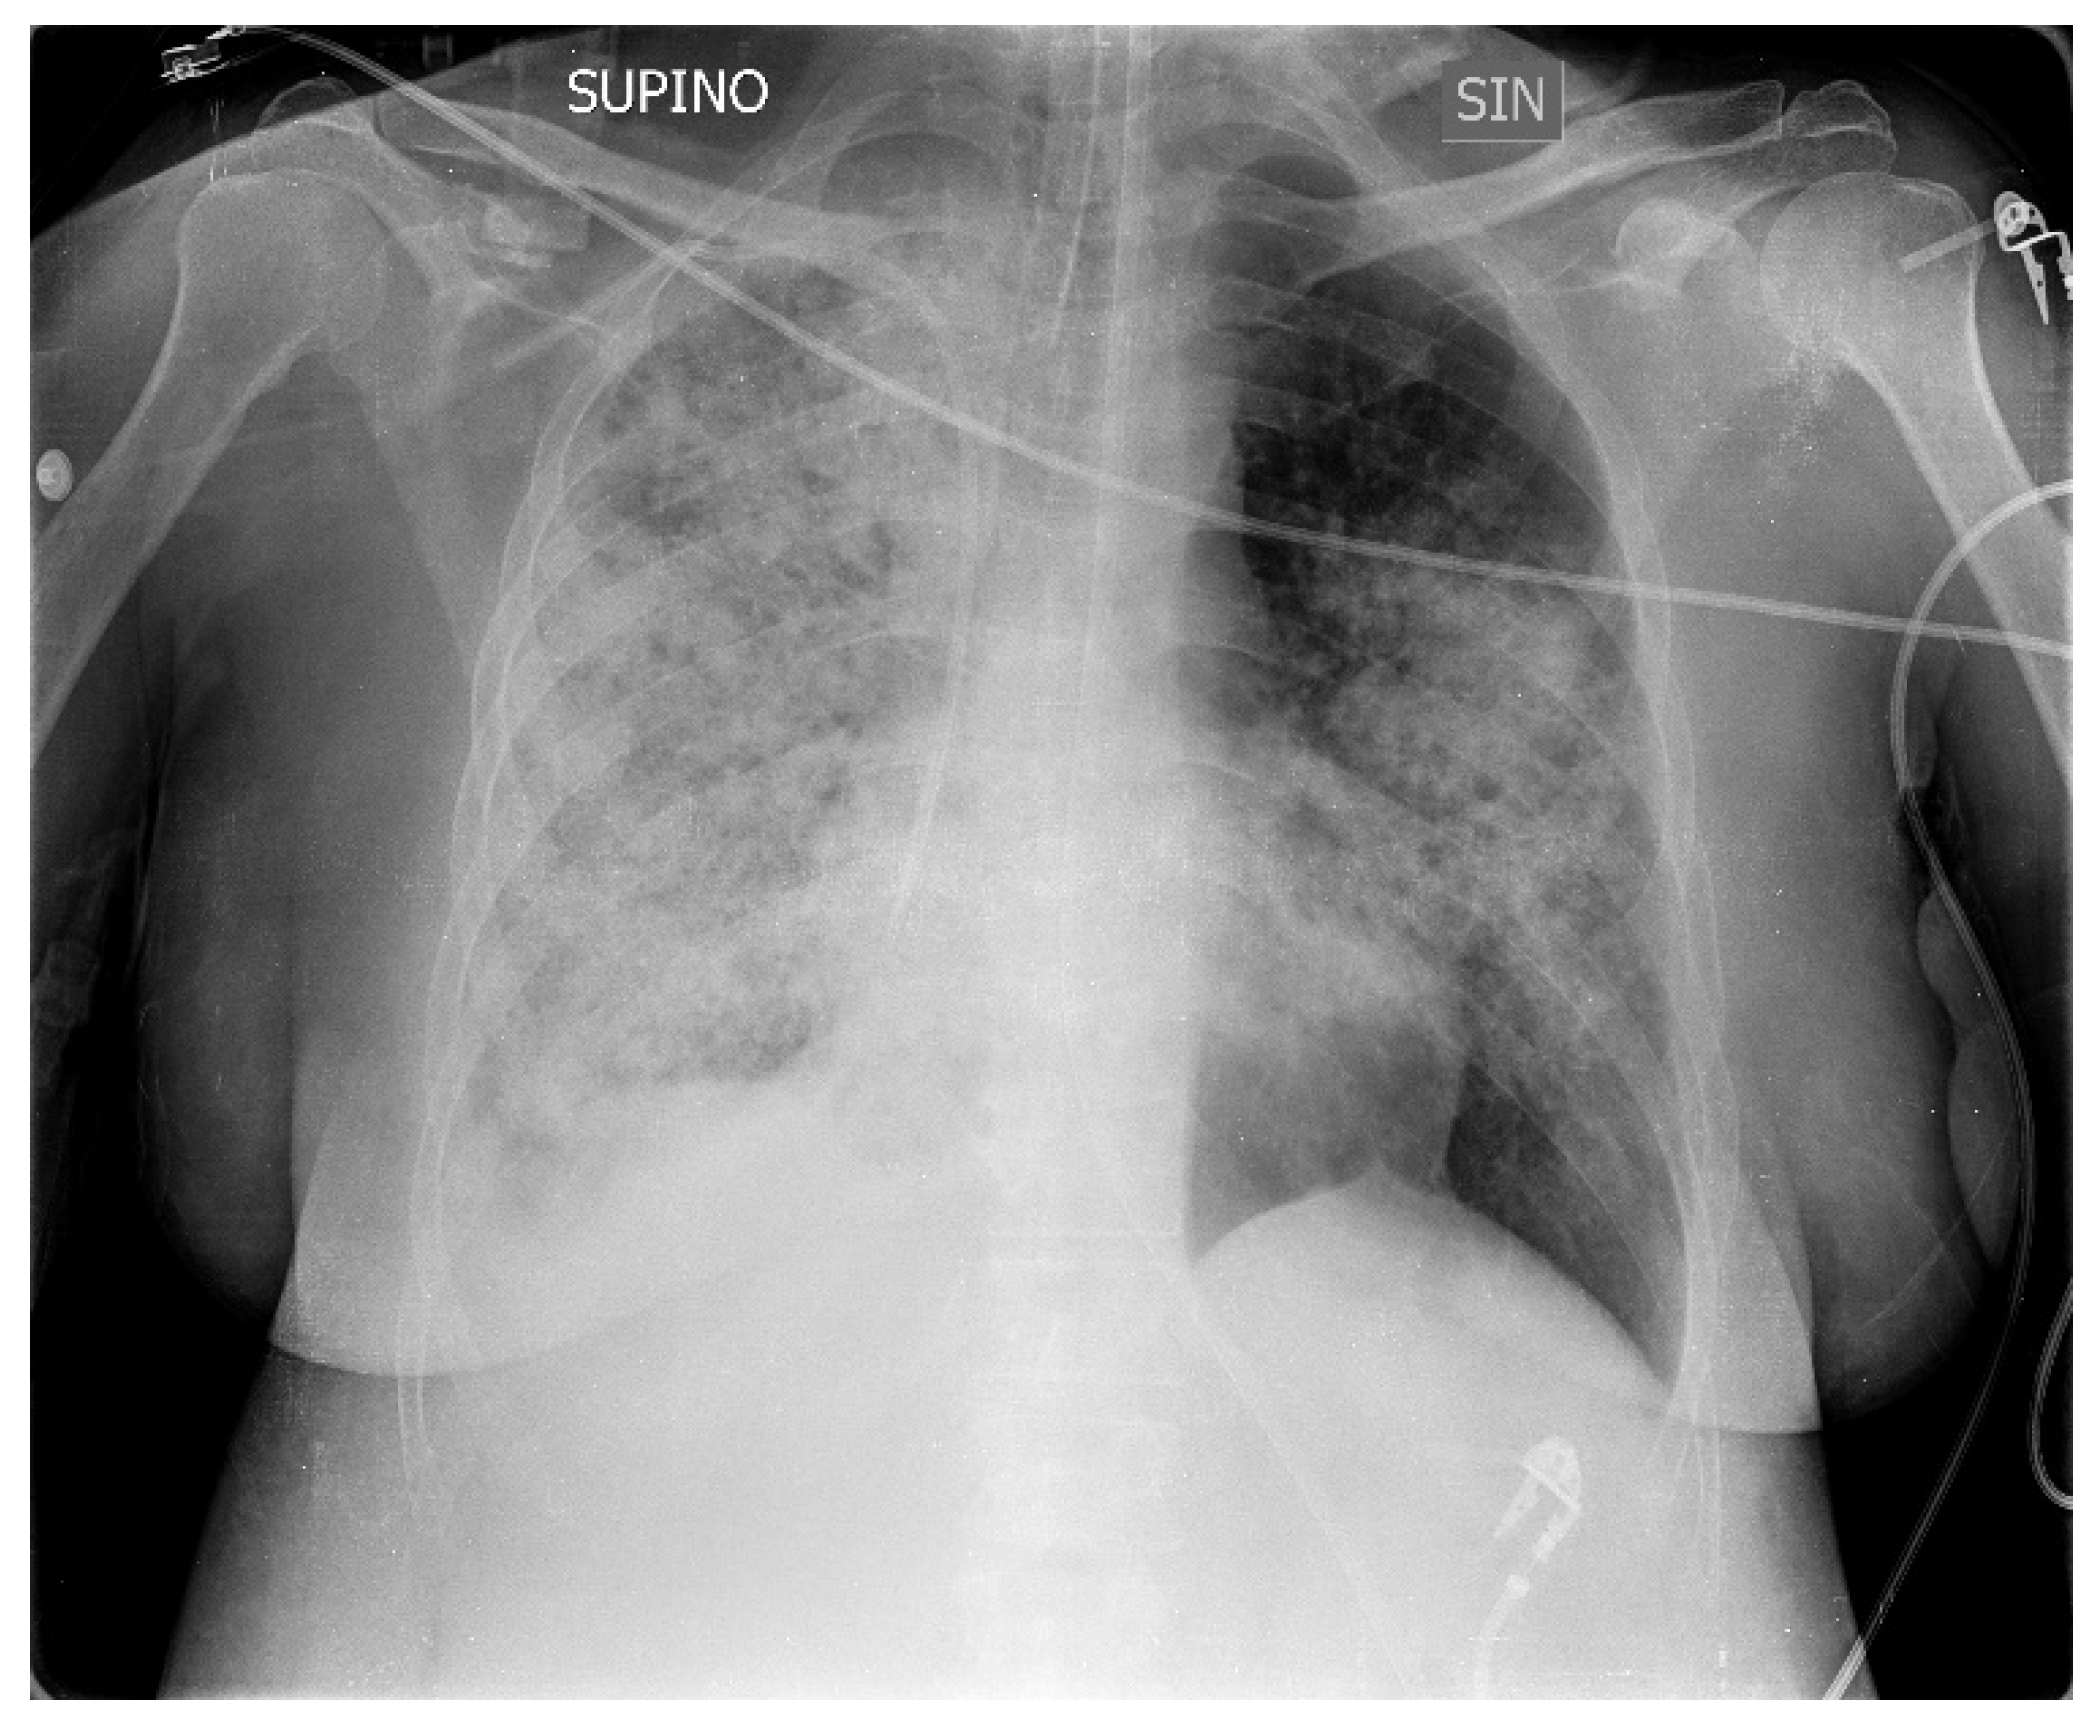

A 50-year-old patient suffering from Down syndrome came to our ED with fever (38 °C), severe respiratory failure, tachypnea and dyspnea, a SpO2 of 82%, sinus tachycardia, and blood pressure of 105/63, and a picture of bilateral pneumonia in the ‘X-ray of the chest with greater involvement of the right lung (Figure 1) The patient came from the medical department of another hospital and the symptoms had started about 10 years ago with cough and low-grade fever. After seven days of home therapy with ceftriaxone and azithromycin for worsening symptoms, she was admitted to hospital with the diagnosis of bilateral interstitial pneumonia. Here, empiric therapy with meropenem, linezolid and caspofungin was started and supplemental oxygen was required.

Figure 1. Chest x-ray upon admission to hospital.